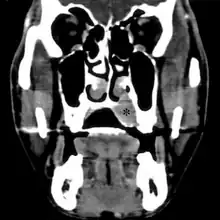

![]() ![]() | |

| Top: Ewing sarcoma of the thigh bone on a child's CT scan Bottom: Extraskeletal Ewing sarcoma of the hard palate | |

MRI will show the full bony and soft tissue extent and relate the tumor to other nearby anatomic structures (e.g. vessels). Gadolinium contrast is not necessary as it does not give additional information over noncontrast studies, though some current researchers argue that dynamic, contrast-enhanced MRI may help determine the amount of necrosis within the tumor, thus help in determining response to treatment prior to surgery. Computed axial tomography (CT) can also be used to define the extraosseous extent of the tumor, especially in the skull, spine, ribs, and pelvis. Both CT and MRI can be used to follow response to radiation and/or chemotherapy. Bone scintigraphy can also be used to follow tumor response to therapy. In the group of malignant small round cell tumors that includes Ewing sarcoma, bone lymphoma, and small cell osteosarcoma, the cortex may appear almost normal radiographically, while permeative growth occurs throughout the Haversian channels. These tumors may be accompanied by a large soft-tissue mass while almost no bone destruction is visible. The radiographs frequently do not shown any signs of cortical destruction. Radiographically, Ewing's sarcoma presents as "moth-eaten" destructive radiolucencies of the medulla and erosion of the cortex with expansion.